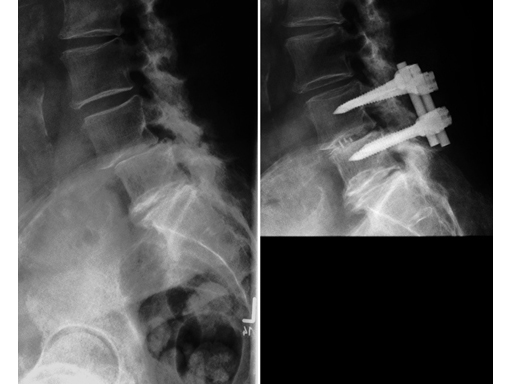

Vertebral Spacer TR (TRAVIOS)

The Vertebral Spacer TR is a radiolucent cage system designed for use in transforaminal lumbar interbody fusion procedures from L1 through L5. The material is PEEK Optima, a biocompatible inert polymer. It enables adequate compression of autograft in and around the implant, thus assuring better stress distribution and load sharing, providing an optimal environment for probiological fusion.

The Vertebral Spacer TR has a kid-ney-shaped footprint. The cranial/caudal surface is convex in the medial lateral direction to provide optimal interface with the lumbar vertebral endplate geometry. The implant has two central holes to receive autograft or other osteo-inductive material and to allow fusion to occur through the implant.